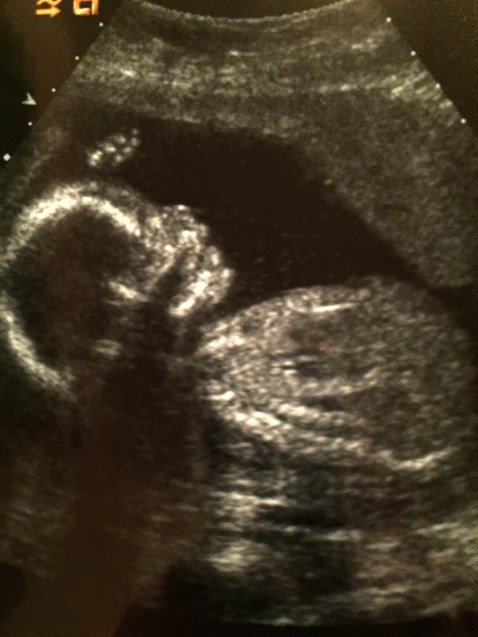

It was like a weight was lifted off me. I was stuck in this cycle of feeling so sad, then feeling guilty for being sad. I told myself being sad over the way my son would look was vain and just terrible and I was not supposed to feel this way. But then she unlocked something so powerful. She allowed me to let go and really grieve. Really go through the stages. I couldn’t really go through the denial, I mean I had this 4D ultra high def ultrasound in front of me that proved this was true. But sadness and anger washed over me and for the first time in my 30 years of life I didn’t run. I embraced it. I sat in it. I held the hand of my husband and grieved. I allowed all the fears and all the hesitations spill out before the Lord. I told Him how I felt about all of this. I fell on my face begging him to take this away. Then slowly and ever so gently He began showing me how we were going to make it through this. How we would be just fine.